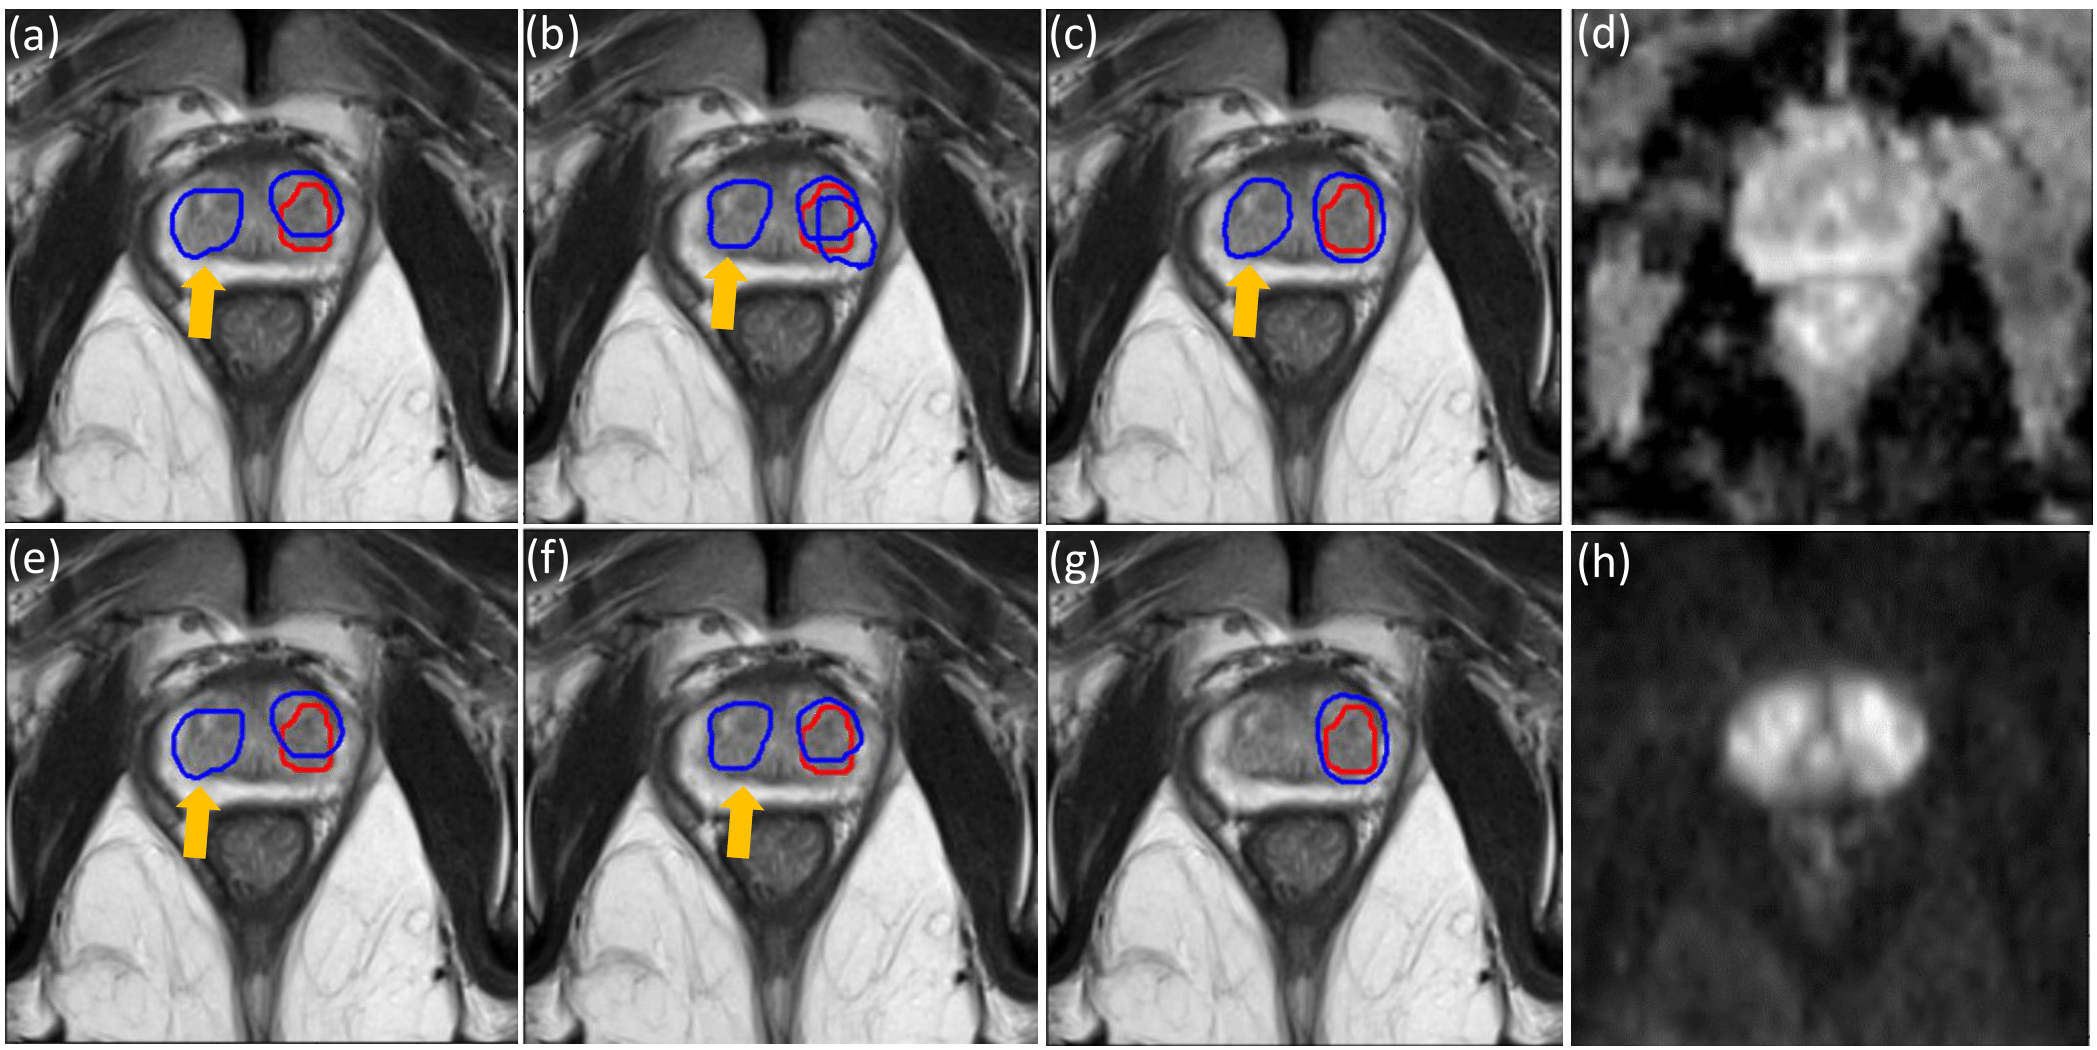

Figure 3: This figure demonstrates the reduction of the lesion-level FPs by changing the lesion-level classification cost Lcost_clssubscript𝐿𝑐𝑜𝑠𝑡_𝑐𝑙𝑠L_{cost\_cls}. The same setting in training was adopted as that in Fig. 2, and all example sub-figures shown here correspond to the performances on one same slice in the test data set (but a different slice with that in Fig. 2. In the first row, threshold=0.7 while threshold=0.95 in the second row. The weighting schemes are summarised as follows: (a,e) αlesion=1,βlesion=1formulae-sequencesubscript𝛼𝑙𝑒𝑠𝑖𝑜𝑛1subscript𝛽𝑙𝑒𝑠𝑖𝑜𝑛1\alpha_{lesion}=1,\beta_{lesion}=1; (b,f) αlesion=3,βlesion=1formulae-sequencesubscript𝛼𝑙𝑒𝑠𝑖𝑜𝑛3subscript𝛽𝑙𝑒𝑠𝑖𝑜𝑛1\alpha_{lesion}=3,\beta_{lesion}=1; (c,g) αlesion=1,βlesion=3formulae-sequencesubscript𝛼𝑙𝑒𝑠𝑖𝑜𝑛1subscript𝛽𝑙𝑒𝑠𝑖𝑜𝑛3\alpha_{lesion}=1,\beta_{lesion}=3. (d) ADC image; (h) DWI b-2000 image.

Fig. 3 shows the example where the FPs were avoided/reduced with αlesion=1subscript𝛼𝑙𝑒𝑠𝑖𝑜𝑛1\alpha_{lesion}=1, βlesion=3subscript𝛽𝑙𝑒𝑠𝑖𝑜𝑛3\beta_{lesion}=3, by comparing Fig. 3 (g) with Fig. 3 (a,b,c,e,f). In the first row in Fig. 3 (c), with relatively lower value of the parameter threshold, the FP still exists with αlesion=1,βlesion=3formulae-sequencesubscript𝛼𝑙𝑒𝑠𝑖𝑜𝑛1subscript𝛽𝑙𝑒𝑠𝑖𝑜𝑛3\alpha_{lesion}=1,\beta_{lesion}=3. In contrast, by comparing Fig. 3 (g) with Fig. 3 (e,f), with larger value of the parameter threshold, the FP was avoided as shown in Fig. 3 (g).